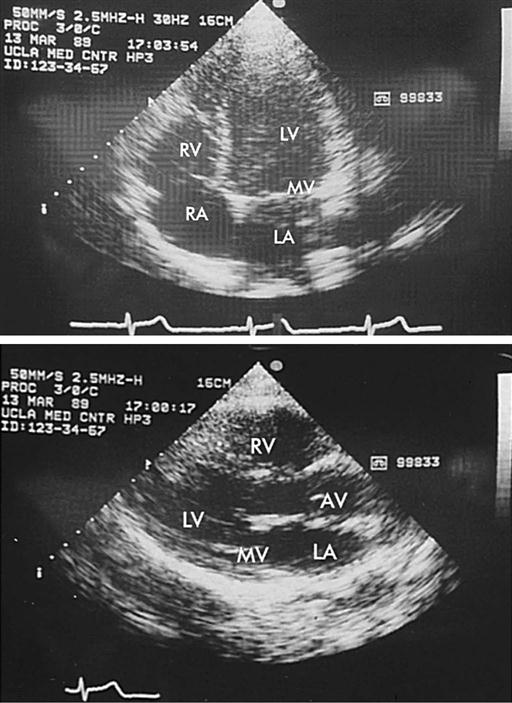

Echocardiography is a noninvasive test that evaluates both the structure and the function of the heart by transmitting sound waves to the heart and measuring those sound waves reflected back to the transducer (Figure 25-11). Sound waves undergo processing by the transducer, which creates visual images of the structure's movements. This test enables assessment of ventricular and valvular function before, during, and after surgery, and determination of the degree of valvular stenosis or regurgitation. It can also demonstrate a tumor, thrombus, or air in the ventricular or atrial cavities. Two-dimensional and color-flow Doppler techniques have greatly enhanced functional assessment of valvular performance and carotid artery stenoses. Echocardiography is the gold standard to diagnose mitral stenosis, and its use to assess other valvular disorders and congenital heart disease is widespread. Transesophageal echocardiography (TEE) also allows evaluation of the effectiveness of valve repairs and other surgical procedures (Table 25-1).